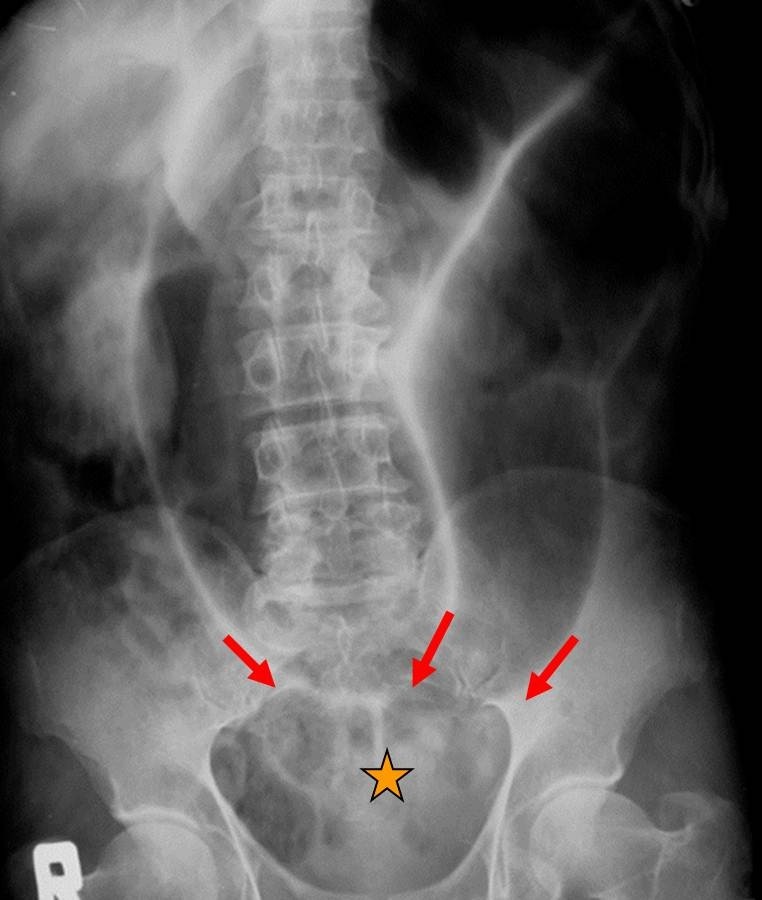

What does the ‘coffee bean’ represent?

A

sigmoid volvulus

- large bowel obstruction caused by sigmoid twisting on itself

px:

- constipation

- abdo blosting

- abdo pain

- vomiting